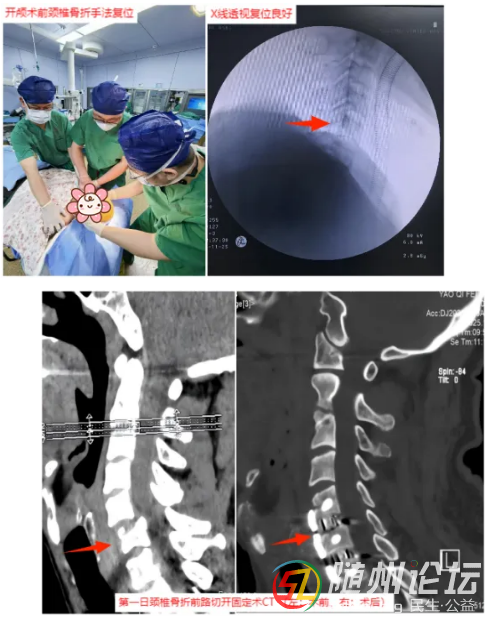

隨即,搶救團隊爭分奪秒。脊柱外科團隊首先對頸椎進行手法復(fù)位,為后續(xù)手術(shù)創(chuàng)造條件;隨后,神經(jīng)外科團隊立即進行開顱手術(shù),精準(zhǔn)清除腦內(nèi)血腫,妥善處理出血點,并將碎裂的顱骨修復(fù)還原;鑒于頸椎骨折仍需穩(wěn)固內(nèi)固定以最大限度保護脊髓功能,緊接著,脊柱外科團隊再次手術(shù),對頸椎進行內(nèi)固定,穩(wěn)定骨折部位,解除對脊髓的壓迫。整個救治過程環(huán)環(huán)相扣,緊張有序。